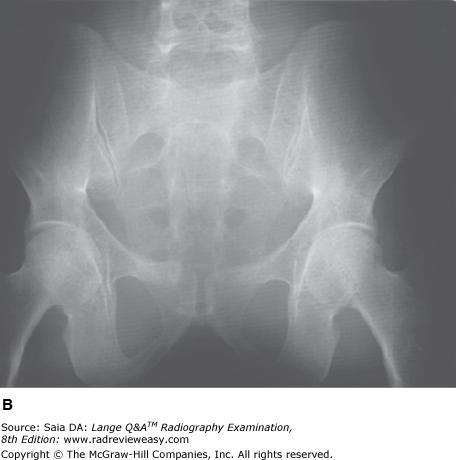

The radiograph of the pelvis shown in the figure below is unacceptable because of

A motion.

B inadequate penetration.

C scattered radiation fog.

D double exposure.

-Radiographic contrast, especially in analog images, can be greatly affected by changes in kilovoltage (see figures below). As kilovoltage increases, a greater number of high-energy photons are produced at the target. These photons are more penetrating, but they also produce more scattered radiation, contributing to lower radiographic contrast as a result of scattered radiation fog. Radiograph B was made using 100 kVp and 18 mAs. Radiograph A was made of the same part using 80 kVp and 75 mAs, all other factors constant. The image details in radiograph A are far more perceptible as a result of the production of less scattered radiation

Which of the following statements is (are) most likely true regarding the figure below?

1.Image A was made using a higher kVp than image B.

2.Image A was made with a higher ratio grid than image B.

3.Image A demonstrates shorter scale contrast than image B.

A 1 only

B 1 and 2 only

C 2 and 3 only

D 1, 2, and 3

-Image A was made using 80 kVp at 75 mAs; Image B was made using 100 kVp at 18 mAs; all other exposure factors remained the same. As kVp is increased, the percentage of scattered radiation relative to primary radiation increases, hence the grayer appearance of image B. Use of optimal kilovoltage for each anatomic part is helpful in keeping scatter to a minimum. The production of scattered radiation will also be limited if the field size is as small as possible. A grid is the most effective way to remove scattered photons from those exiting the patient. Grids are designed to selectively absorb scattered radiation while absorbing as little of the primary radiation as possible. Images produced with higher ratio grids will possess fewer grays than those made with lower ratio grids.